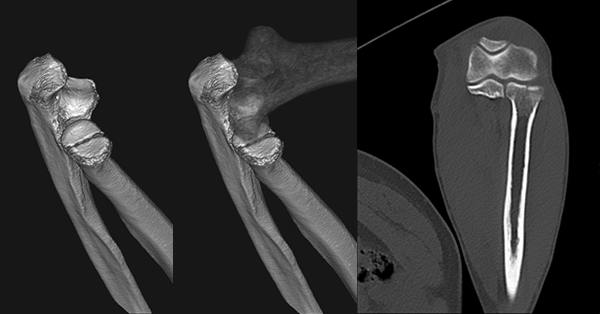

臨床画像例

中山氏 IPVは被ばく低減に役立っています。

当院では、体幹部は平均的にガイドライン*2比で50%近く低被ばくの条件で撮影していますが、読影の先生にも問題なく診断して頂いています。低被ばくに撮影することは、患者さんのメリットに繋がります。当院では、さらに患者さんに安心していただくため、被ばく線量を集計して患者さん向けの説明ツールを作っています。